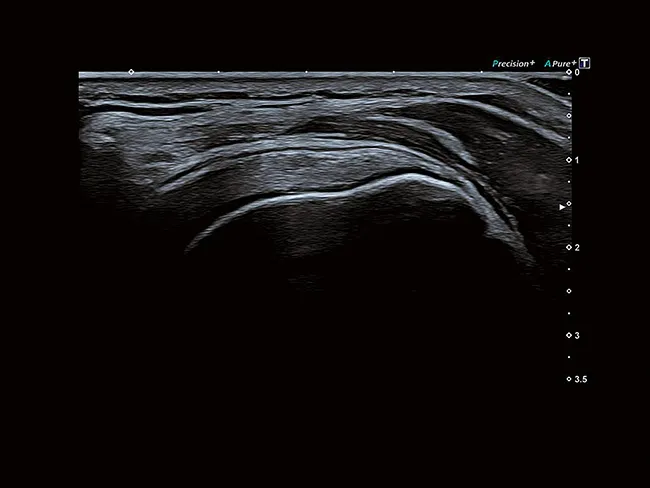

Precision + обеспечивает сглаженные изображения с четкими очертаниями контуров, повышенную однородность изображения и уменьшение помех.

ApliPure + обеспечивает повышенную контрастность изображения и уменьшение спекл-шума для улучшения визуализации.

Легкие датчики, разработанные для повышения эффективности, отличаются исключительной клинической универсальностью, эргономичными формами и тонкими сверхгибкими кабелями.